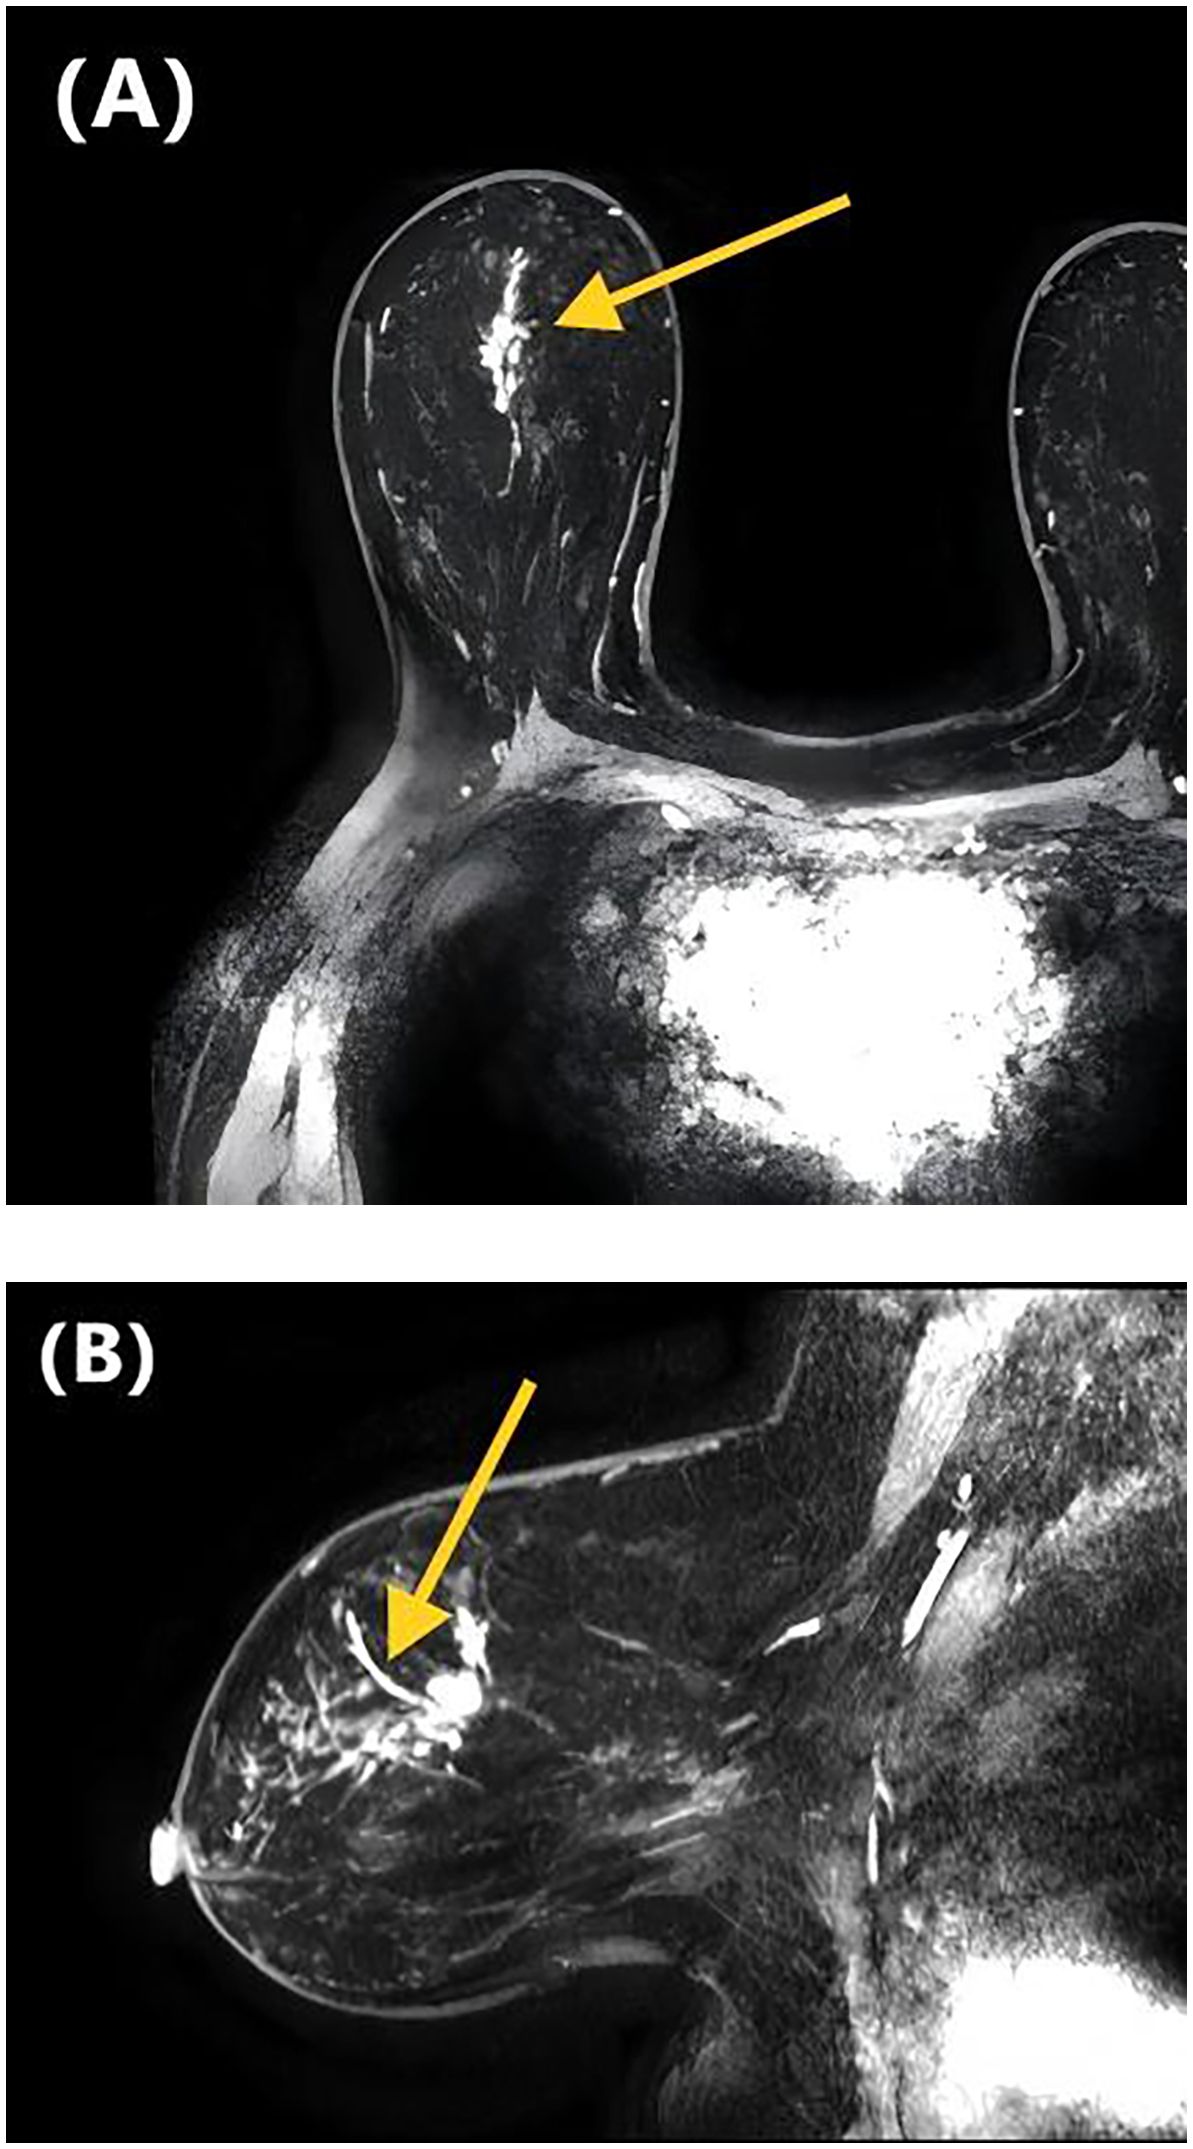

Figure 1. DCE-MRI images of a 47-year-old woman with invasive ductal carcinoma of the right breast. Axial contrast-enhanced image (A) and sagittal contrast-enhanced image (B) show non-mass-like enhancement with the linear distribution. Lymphovascular invasion was confirmed at the histopathological examination.

Table 2 presents the GVIF analysis used to assess multicollinearity. The regression model demonstrated an absence of significant multicollinearity, as all adjusted GVIF values were below 2.24 except for PR status. Although the GVIF for PR status exceeded 2.24, it remained below the 3.16 tolerance threshold, indicating acceptable collinearity levels. After controlling for confounding factors through multivariate logistic regression analysis, four risk factors associated with LVI formation were identified (Table 3). Patients aged ≥45 years (OR = 0.406, 95% CI: 0.191-0.844, P = 0.017) and those with higher ADC values (OR = 0.133, 95% CI: 0.017-0.825, P = 0.041) had a lower risk of LVI formation. Among the NME distribution patterns, patients with linear distribution had a significantly higher risk of LVI positivity compared to those with focal distribution (OR = 13.540, 95% CI: 1.390-172.644, P = 0.030) (Figures 1, 2), while no statistically significant differences were found for segmental, regional, multiple region, or diffuse enhancement patterns (all P > 0.05). Regarding molecular subtypes, compared to the Luminal A subtype, patients with Luminal B (OR = 5.081, 95% CI: 1.326-33.859, P = 0.039), HER2 overexpression (OR = 9.378, 95% CI: 1.922-71.460, P = 0.012), and triple-negative subtype (OR = 11.599, 95% CI: 2.043-96.710, P = 0.010) had a significantly higher risk of LVI formation.